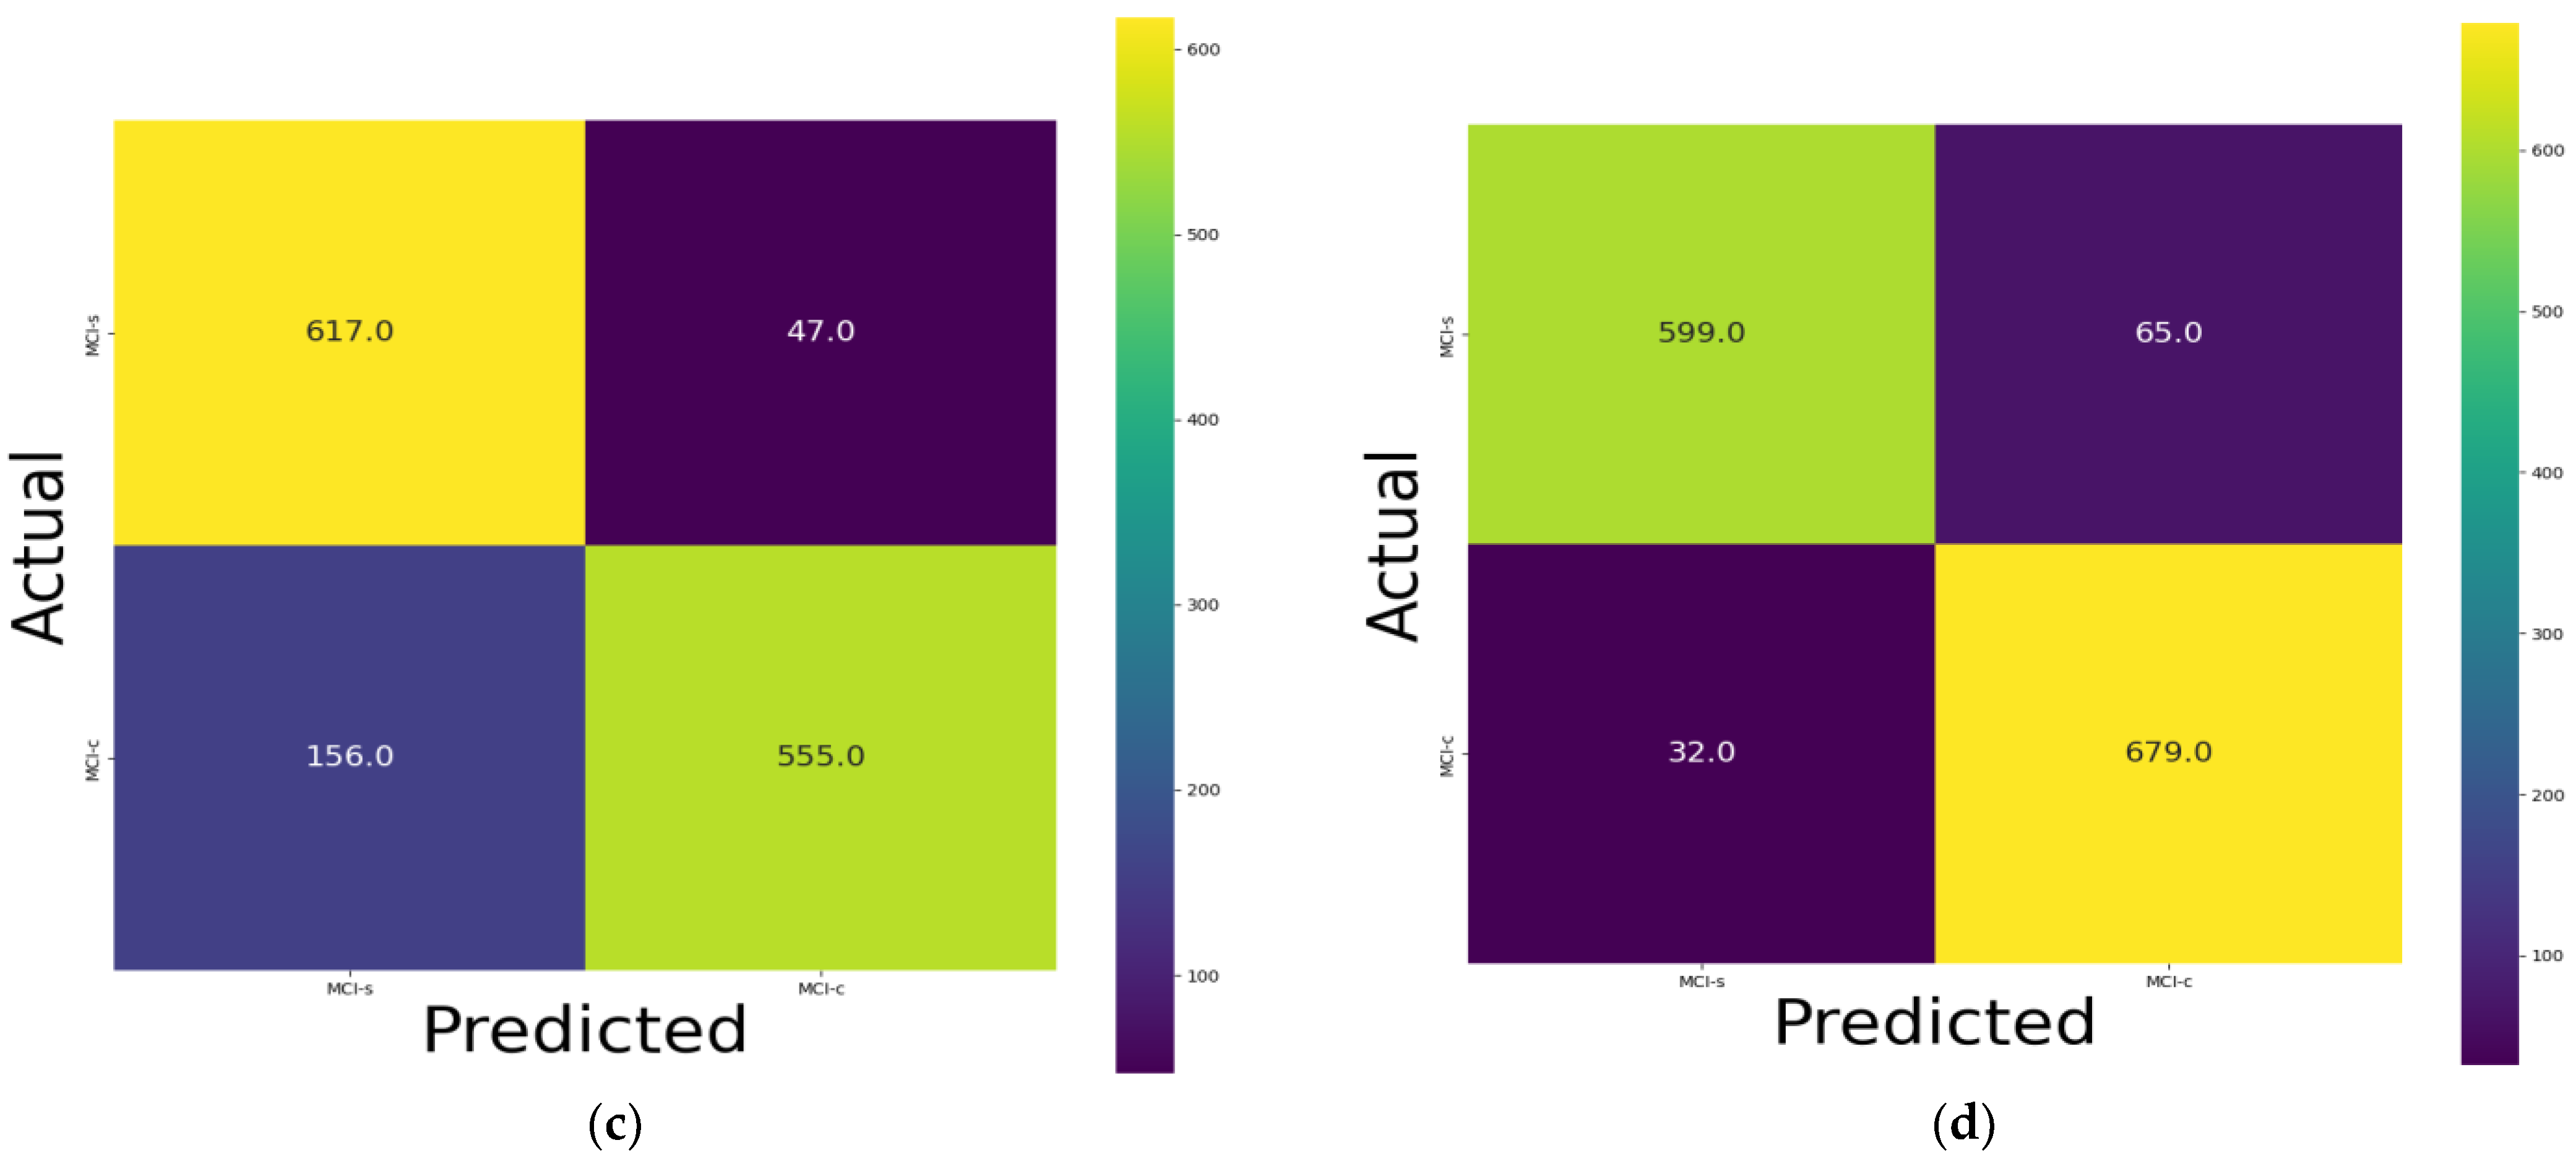

3.1. Classification Performance on 18F-FDG-PET

3.2. Ablation Study